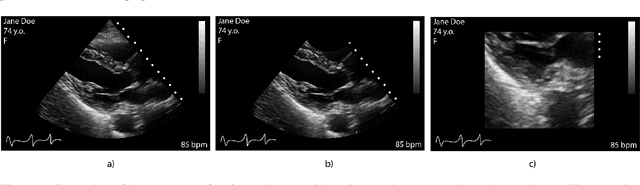

Abstract:Leveraging medical record information in the era of big data and machine learning comes with the caveat that data must be cleaned and deidentified. Facilitating data sharing and harmonization for multi-center collaborations are particularly difficult when protected health information (PHI) is contained or embedded in image meta-data. We propose a novel library in the Python framework, called PyLogik, to help alleviate this issue for ultrasound images, which are particularly challenging because of the frequent inclusion of PHI directly on the images. PyLogik processes the image volumes through a series of text detection/extraction, filtering, thresholding, morphological and contour comparisons. This methodology deidentifies the images, reduces file sizes, and prepares image volumes for applications in deep learning and data sharing. To evaluate its effectiveness in the identification of regions of interest (ROI), a random sample of 50 cardiac ultrasounds (echocardiograms) were processed through PyLogik, and the outputs were compared with the manual segmentations by an expert user. The Dice coefficient of the two approaches achieved an average value of 0.976. Next, an investigation was conducted to ascertain the degree of information compression achieved using the algorithm. Resultant data was found to be on average approximately 72% smaller after processing by PyLogik. Our results suggest that PyLogik is a viable methodology for ultrasound data cleaning and deidentification, determining ROI, and file compression which will facilitate efficient storage, use, and dissemination of ultrasound data.